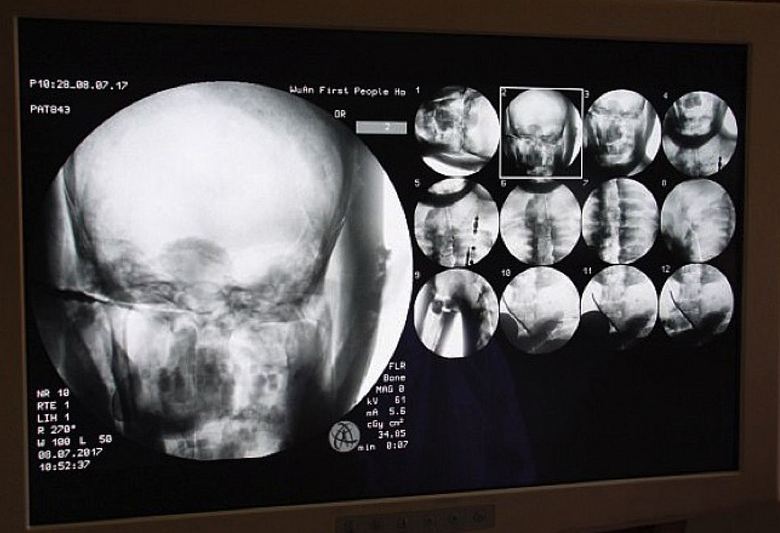

Gli scienziati hanno accettato volentieri, perché erano loro stessi interessati questo interessante studio. E l’8 luglio di quest’anno, proprio nel tempio Dinghui, fu eseguita una tomografia dell’antica mummia buddista monaco. I medici hanno portato qui l’attrezzatura necessaria e hanno speso scansione del contenuto interno della mummia. Erano scioccati esclusivamente tutto, cioè non solo studiosi, ma anche monaci, pellegrini che si sono riuniti su questo senza precedenti per il monastero l’evento, ovviamente, e gli operatori dei media. Si è scoperto che le articolazioni, le ossa e i denti di un monaco millenario Tsa Xian sono come quelli di un vivente persona. Inoltre, il suo cervello era perfettamente conservato.

È semplicemente incredibile, ha commentato il dottor Wu. Yongqing (Wu Yongqing), che eseguì direttamente la tomografia mummie. Non riesco nemmeno a credere come le parti principali di una persona imbalsamato più di mille anni fa, conservato in stato “sano”, anche il cervello! Ma i monaci stessi non lo sono non vedono nulla di soprannaturale in questo, sono sicuri che il Maestro Tsy Xian non è morto affatto, è semplicemente entrato in uno stato di samadhi, da che un giorno si sveglierà sicuramente. Dopotutto, scannerizzare una mummia ha mostrato: il suo corpo è pronto per una nuova vita …